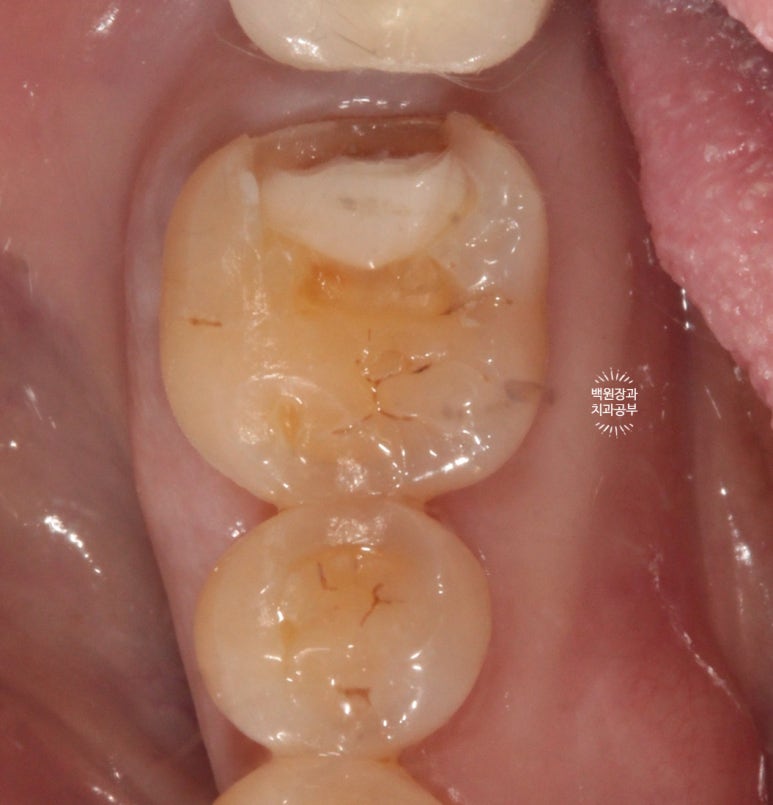

기존의 골드 인레이를 제거하였을 때, 하방에 존재했던 광범위한 2차 우식을 관찰할 수 있었어요.

어디까지 제거하냐면, 단단한 치질 (상아질)이 확보될 때 까지입니다.

(꼭 하얀색이 아닐 수 있어요. 보통 약간 누리끼리 합니다.)

처음에는 high speed angle을 이용하여 경계부를 제거해 줍니다.

이 후 치아 내부의 신경관 노출을 최소화 하기 위해서 마무리는 손기구 (hand instrument)로 진행!

결과적으로 2차 우식을 조심히 제거하여 치아 내부의 신경 노출을 피할 수 있었습니다.!!!

너무 깊었기 때문에 치수를 진정시킬 수 있을 glass ionomer를 base로 사용하여 이장해 주었습니다.

쉽게 얘기하면, 신경이 노출되진 않았지만 너무 가까우므로 단열재를 설치해 주었다! 정도로 이해해주세요.

남은 빈 공간을 단단한 레진을 사용하여 채워줍니다.

레진 코어라고 해요!